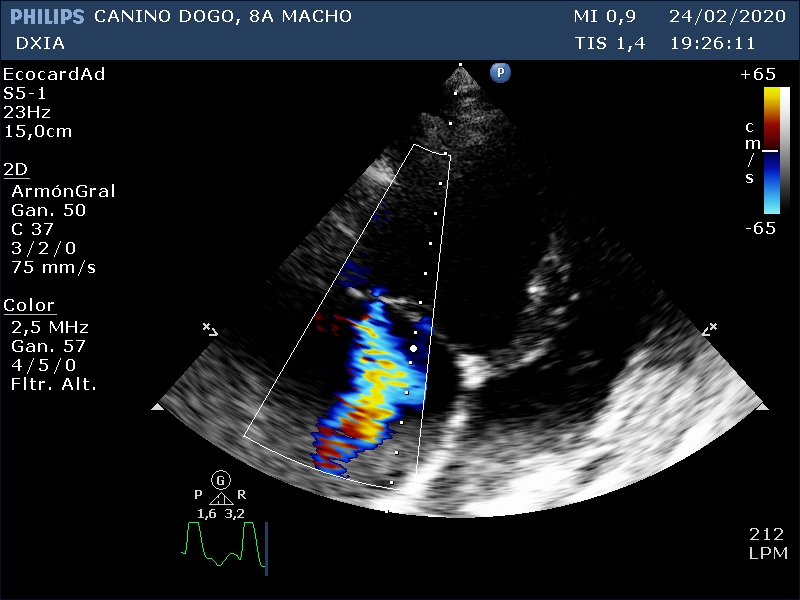

Corte apical izquierdo 4 cámaras. Observamos aumento de cámaras cardiacas, cambios grosores paredes

Corte apical izquierdo 4 cámaras. Doppler color en VM observando jet turbulento

Leve engrosamiento nodular valva septal de la VM

Comentario respecto al estudio ecocardiográfico:

- Agrandamiento de cámaras derechas e izquierda con disminución grosores paredes cardíacas.

- Valva septal de la VM levemente engrosada con patrón nodular ¿degeneración?

- Varios indicadores de cambios compatibles con fenotipo de CMD.

- ECG fibrilación atrial.